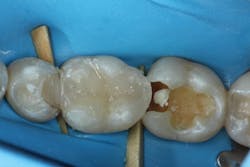

For these neighboring restorations, the choice was made to restore the teeth one at a time using a sectional matrix system (Triodent V3 Ring; Ultradent Products). The advantage of restoring only one tooth at a time is that it is possible to perfect the interproximal contours of the first restoration prior to initiating the neighboring restoration. In this case, the distal marginal ridge of tooth No. 30 encroached into the mesial box of No. 31 after the initial fill (figure 7).

Figure 7: Second layer of composite placed with the marginal ridge of tooth No. 30 encroaching on the box of No. 31

In order to recontour the proximal contact without gauging the composite, a medium grit flexible disc (FlexiDisc; Cosmedent Inc.) was used (figures 8 and 9). Other clinicians prefer to restore both teeth at the same time and attempt to evenly distribute the space by careful placement of the sectional matrices or by holding the place of the unrestored tooth with a ball of Teflon tape.

Figure 8: Proximal contacts adjusted with medium grit flexible polisher (FlexiDisc; Cosmedent Inc.)

Figure 9: Favorable proximal contours achieved on the distal of tooth No. 30